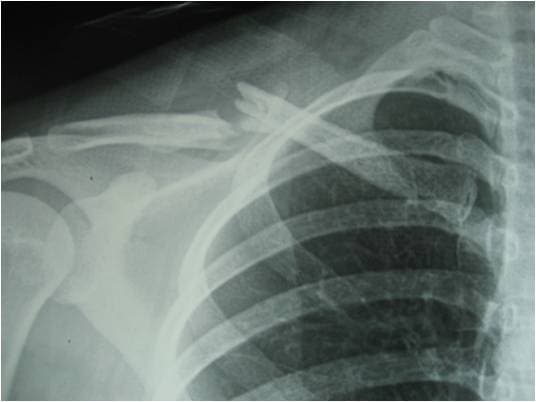

Tuy nhiên, để chẩn đoán chính xác tình trạng gãy xương đòn vai của người bệnh, bác sĩ không chỉ dựa vào những triệu chứng lâm sàng mà còn cần thực hiện một số phương pháp khác như chụp X-quang thẳng nghiêng xương đòn để xác định được vị trí gãy, đường gãy.

Nếu cần những kết quả chi tiết hơn về tình trạng gãy, bác sĩ có thể chỉ định chụp CT. Trong trường hợp người bệnh có chỉ định mổ, cần thực hiện thêm các loại xét nghiệm khác.